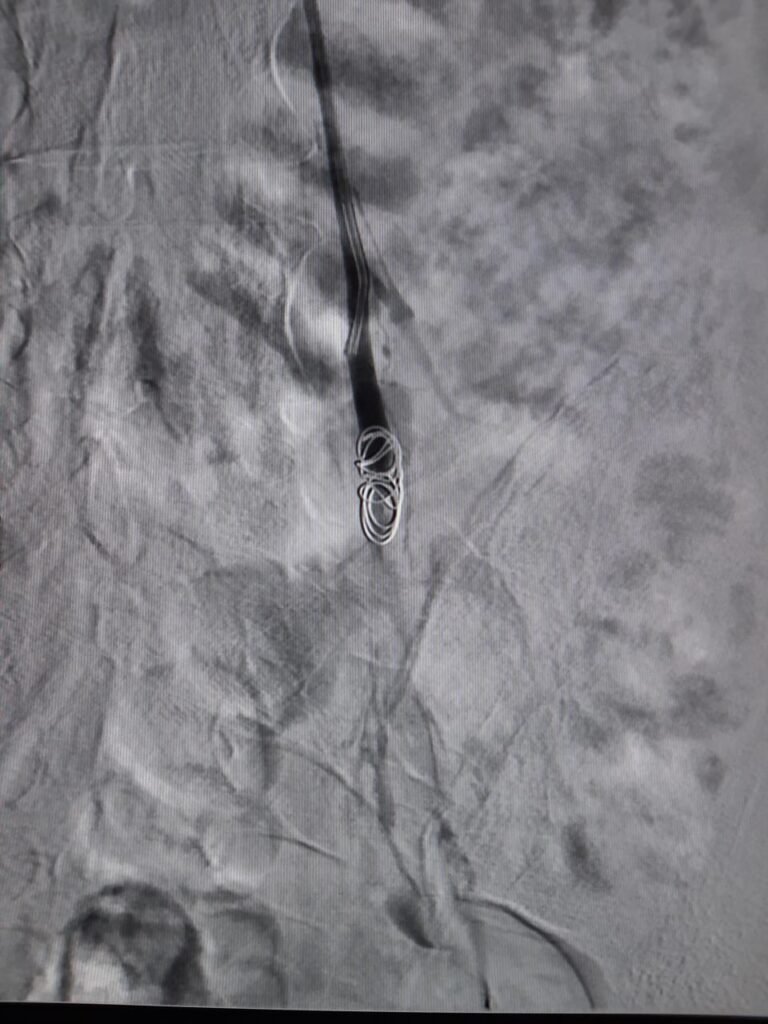

La technique consiste à introduire un cathéter par voie veineuse, généralement au niveau de l’aine, puis à naviguer jusqu’aux veines ovariennes et pelviennes dilatées sous contrôle radiologique. Une fois les vaisseaux pathologiques identifiés par angiographie, des agents emboliques (coils métalliques, bouchons vasculaires ou colles biologiques) sont déployés avec précision pour bloquer définitivement le reflux veineux. Cette occlusion force le sang à emprunter d’autres voies de drainage physiologiques, éliminant ainsi la congestion pelvienne responsable des douleurs.